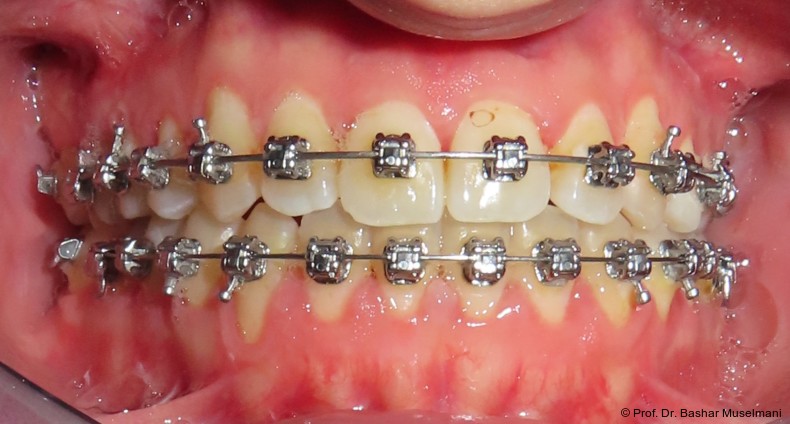

Apparative Versorgung

Die Behandlung erfolgte mittels einer festsitzenden Multibracketapparatur unter Verwendung passiver selbstligierender Brackets (Damon Ultima System) im Ober- und Unterkiefer.

Zur sagittalen Korrektur wurden intermaxilläre Klasse III-Gummizüge eingesetzt.

Zu Beginn der Nivellierungsphase wurden in beiden Kiefern 0.013" CuNiTi-Bögen eingesetzt (Abb. 4a–e).